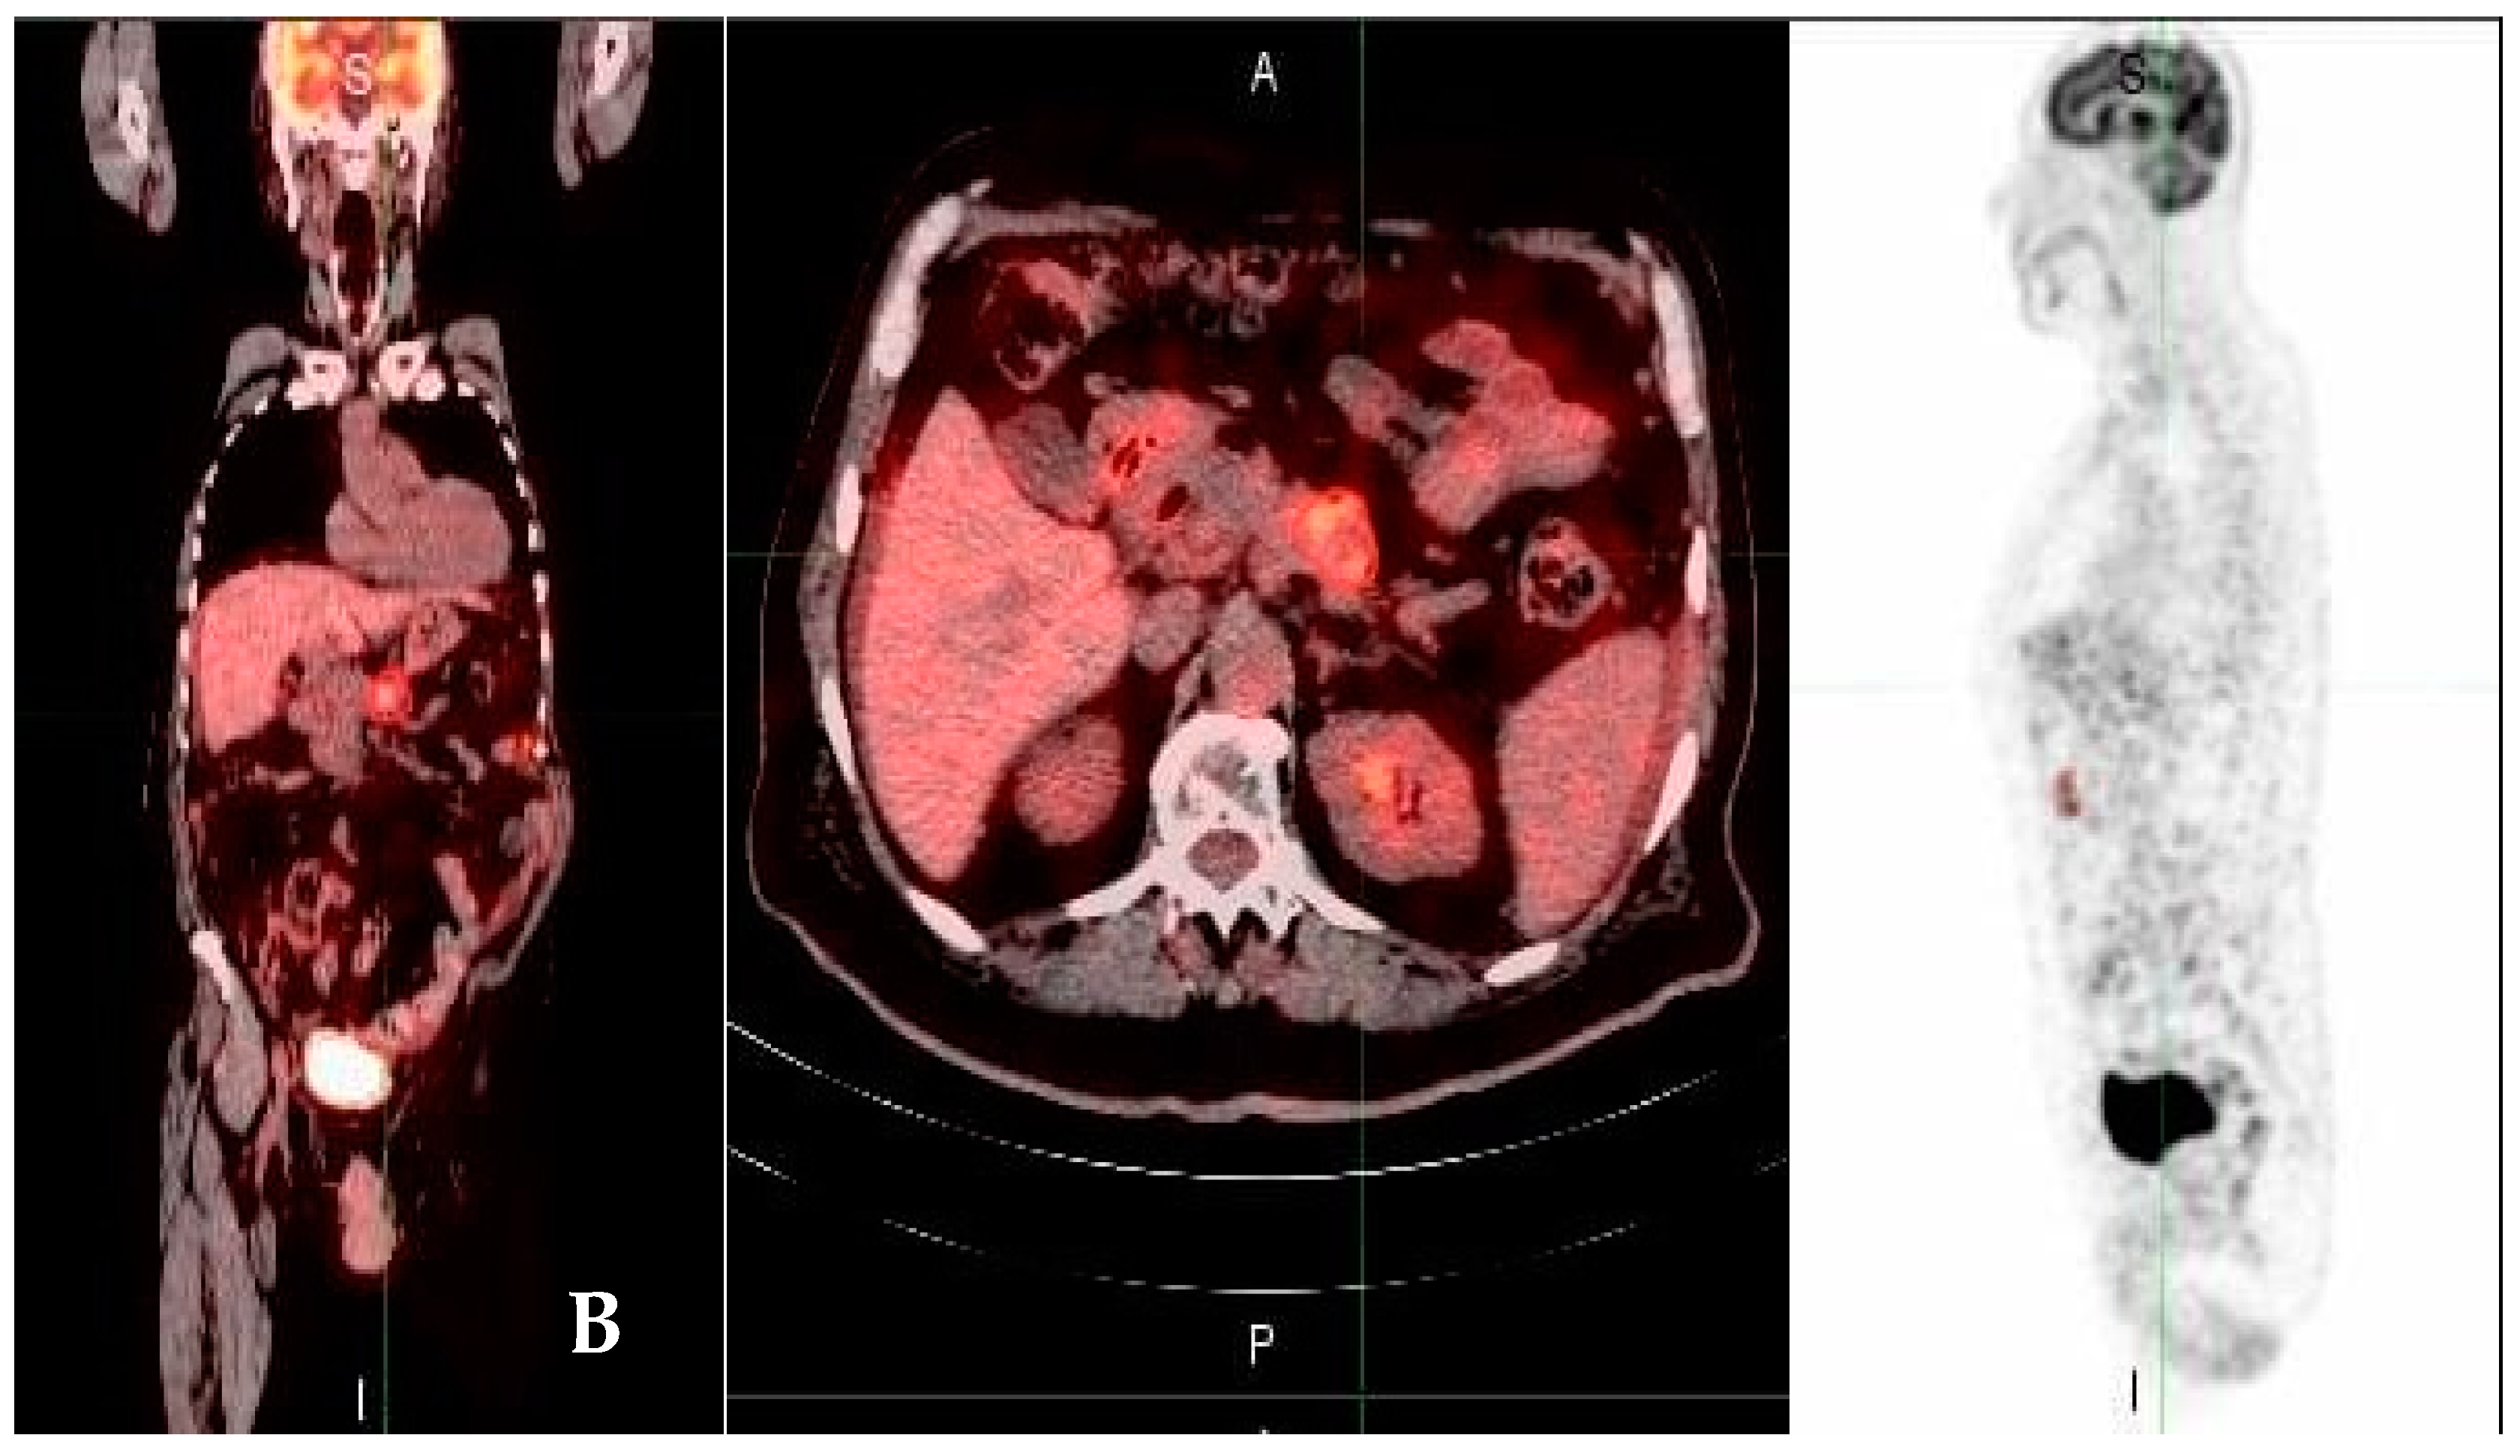

3.2. FDG PET/CT Parameters Results

3.3. Tumor Glycolytic Activity